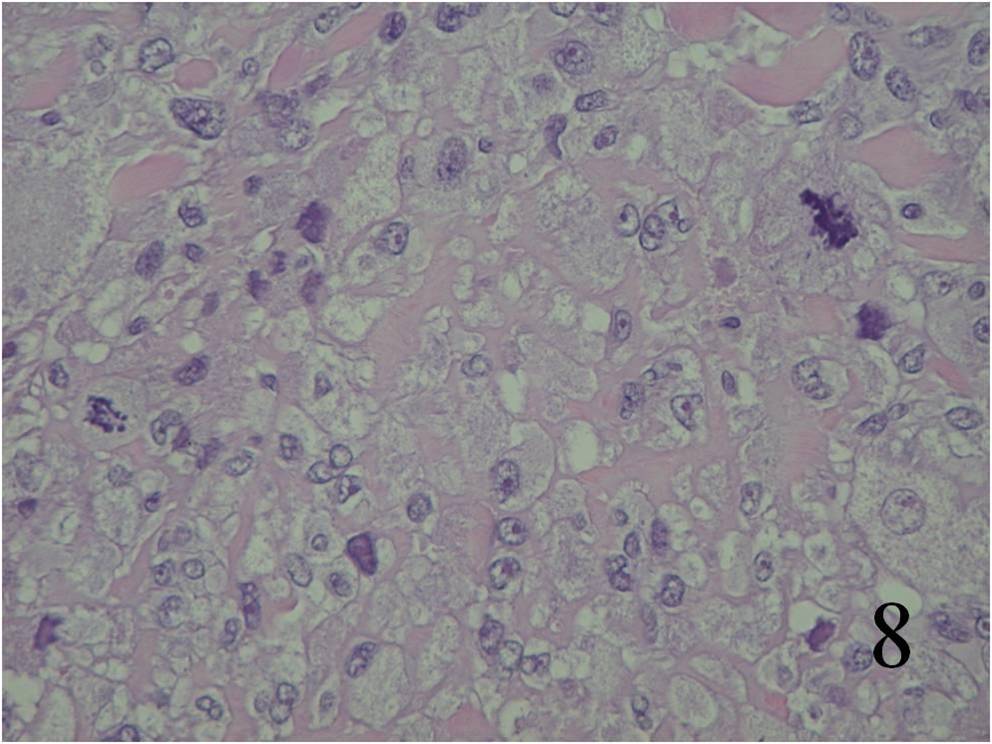

Microscopic

Large variation in differentiation, from obvious smooth muscle differentiation to an appearance similar to MFH (Fig. 7,8)

Moderately cellular, with elongated cells and eosinophilic cytoplasm

Cells are arranged in fascicles, with giant cells (giant cells often resemble osteoclasts)

The nuclei look elongated and can have an appearance similar to a corkscrew with round ends

Fig. 7 Microscopic: Low and High (Fig. 8) power magnification of a leiomyosarcoma showing palisading spindle cells; with eosinophilic cytoplasm. Immunohistochemical stains for leiomyosarcoma are positive stain for actin (Fig. 9) and desmin (Fig. 10)